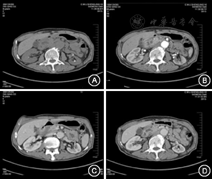

(1)病例特点:患者女性,60岁,以"上腹部疼痛20 d"于2015年8月11日收入我科,伴发热寒战,最高达39.7 ℃,查体:右上腹压痛阳性,无反跳痛及肌紧张。既往史:右乳腺癌改良根治术术后1年。实验室检查:肿瘤标志物CA19-9稍高,其余化验结果未见明显异常。完善增强CT见胆囊壁明显增厚,周围多发渗出影;增强扫描囊壁强化不均;局部见结节样突入胆囊腔(图5)。PETCT考虑恶性(图6)。(2)治疗:腹腔镜胆囊切除术,术中冰冻回报:考虑炎症,待石蜡。(3)术后病理诊断为慢性胆囊炎伴炎性肌纤维母细胞瘤样病变。(4)术后电话随访18个月未见明显复发表现,恢复良好。